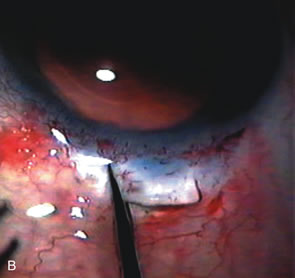

Preparation of the Scleral Tunnel Creation of the scleral tunnel is a crucial step in successful wound construction. If the resultant scleral flap is too thin and a tear occurs during closure, excessive filtration with all the risks of hypotony will occur. When the scleral flap is too thick due to a deep plane, premature entry into the anterior chamber with subsequent intraoperative iris prolapse and bleeding occurs. During surgery, this results in a shallow anterior chamber with excessive iris and corneal trauma. Typically, a 50% to 75% depth flap seems to be safest for development of the flap and scleral tunnel. Additionally, if the scleral tunnel incision is extended too far into clear cornea, corneal striae inhibit adequate visualization during phacoemulsification. After achieving approximately 75% scleral depth, extend the scratch incision for 3 mm and use a crescent blade to tunnel 1 mm into clear cornea (Fig. 13). During development of the tunnel, keep the underside of the crescent blade flat against the curvature of the eye to establish the proper plane. Direct a 3-mm keratome to the end of the scleral pocket and with a dimpling-down maneuver enter the anterior chamber. This completes a triplanar incision, a critical prerequisite for small-incision wound stability.

Pupil management Inadequate visualization of the anterior capsule due to miosis may lead to a series of surgical mishaps. Inadequate dilation of the pupil is a common problem for all cataract surgeons and occurs most frequently in glaucoma patients. In these patients, the pupils are not only small but also bound down to the lens with pigment and fibrous tissue adherent to the anterior capsule. As these adhesions are lysed, pigment and blood may be liberated into the anterior chamber, further interfering with the surgeon's view. If the pupil is less than 4 mm after preoperative and intraoperative pharmacologic means, the surgeon must be prepared to use ancillary surgical methods of pupil enlargement (Fig. 14). The methods of pupil enlargement associated with phacoemulsification are different than those required for ECCE. Both are thoroughly covered in this chapter because miosis is still a common problem encountered when performing cataract surgery in glaucoma patients. The most popular methods of pupil enlargement associated with phacoemulsification are two-handed pupil stretching techniques,181 pupil expanders,182 and iris hooks,183,184 (Table 4) Microsphincterotomies created by mechanical iris stretching are preferable to incisional sphincterotomies185 made with scissors. If the sphincter is completely transected by scissors or if stretching is too vigorous, the pupil will remain flaccid postoperatively and an atonic pupil develops.186 If a can-opener capsulorhexis is used, pupil capture is more common as the IOL migrates and the cut end of the capsule adheres to the iris. Iridocapsular adhesions serve as a bridge for the migration of macrophages onto the surface of the IOL preventing optimal vision. Properly performed sphincterotomies along with a complete capsulorrhexis allow excellent postoperative pupil function as long as postoperative inflammation is minimal and adhesions do not occur.

Phacoemulsification Once the continuous curvilinear pupil is enlarged to a minimum of 6 mm, perform a capsulorrhexis, followed by hydrodissection (Fig. 15). The size of the capsulorrhexis varies depending on the type and size of the IOL. The use of dyes to stain the anterior capsule significantly helps visualize the poorly seen anterior capsule facilitating completion of the capsulorrhexis.187,188 Hydrodissection allows separation of the cortex from the capsule allowing rotation of the nucleus. These maneuvers are essential for easy nucleus rotation and are especially critical for patients with weak or fragile zonules. Make a paracentesis site in the temporal cornea.

At this point, incise only one side of the scleral tunnel to create a partial scleral flap. This allows phacoemulsification without creating striae in the cornea that inhibit visualization but prevents excessive outflow. With a 30-degree tip phacoemulsification handpiece, emulsify and crack the nucleus with a two-handed divide-and-conquer technique. Each quadrant is fragmented with the emulsifier and removed on pulse mode, leaving the epinucleus, which is removed with aspiration and low-power ultrasound (Fig. 16). If the cataract is very dense, use a chopping technique or a Kelman tip. Surgeons comfortable with nuclear cracking techniques have an advantage working with very dense nuclei. Employ the irrigation and aspiration handpiece to remove residual cortex, and clean the posterior capsule with low vacuum. A U-shaped cannula is often very helpful for removing residual subincisional cortex. After irrigation, aspiration, and capsule vacuum, inject viscoelastic into the anterior chamber and expand the capsular bag.